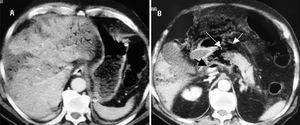

La presencia de necrosis intestinal, asociada a otro proceso abdominal simultáneo que pueda originar AVP en la TC de abdomen, debe sospecharse cuando los niveles plasmáticos de creatinfosfocinasa y lactato son extremadamente altos o existe acidosis metabólica grave inexplicable13,16, especialmente si la TC abdominal muestra signos de isquemia intestinal como engrosamiento de la pared del intestino con o sin signo de diana, neumatosis intestinal, AVP, edema mesentérico, ascitis, tromboembolismo mesentérico o infartos de órganos abdominales1,18 (fig. 3).

Figura 3. Diagrama de flujo de diagnóstico y tratamiento de pacientes con aire venoso portal hepático (modificada de Hou et al2). El símbolo + significa hallazgos positivos y el signo - significa sin hallazgos. TC: tomografía computarizada; CPK: creatinfosfocinasa.